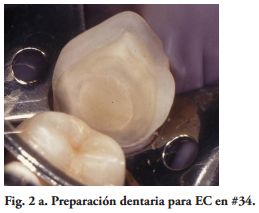

Las paredes internas de la corona dentaria y de la cámara pulpar, deben tener una divergencia hacia oclusal mayor de 60 y si presentan depresiones o zonas retentivas, deben rellenarse con cemento de ionómero de vidrio. El operador, dispensa una fina capa del mismo cemento en el piso cameral. En este estudio cuatro preparaciones tenían 3 paredes coronarias (Figs. 1b, 2a), cuatro 2 paredes (Fig. 3a) y en 2, las restauraciones abarcaban 4 paredes coronarias.

Por su parte, varios estudios clínicos, concluyeron que el remanente coronario es el factor más importante en el éxito clínico del DET (18-21). Por lo tanto, un criterio conservador es esencial en la preparación dentaria para un EC. Toda la superficie oclusal debe ser cubierta por la restauración, teniendo en cuenta la función oclusal del paciente. Los onlays transmiten fundamentalmente, fuerzas compresivas en la interfase adhesiva restauración - diente, mejorando el comportamiento biomecánico (22-24). Para este procedimiento restaurador fue sugerido un espesor oclusal de 3 mm. (25) y aumentando el mismo la resistencia a la fractura sería más alta (26). Además. si las paredes vestibular y/o palatina o lingual, tienen un espesor mayor de 2.0 mm., un chamfer de 1.2 mm. en oclusal de estas paredes, podrían tener un efecto zuncho o abrazadera, aumentando la resistencia a la fractura de los dientes y la retención de la restauración (Figs. 3a, 4a).